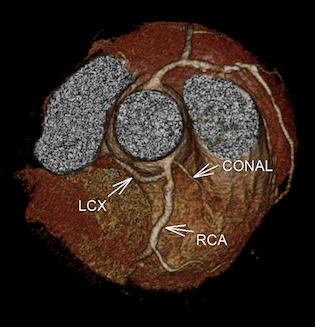

CASE 1- Coronary anomaly- LCX FROM RCA

Anomalous origin of the Left Circumflex artery from Right Coronary artery identified by imaging with Multidetector Computed Tomography

On MDCT angiography, left coronary artery was seen to arise from the left sinus of valsalva which further coursed along the anterior interventricular groove as LAD. RCA was seen to be arising from anterior aortic sinus with its normal course along right atrio-ventricular (AV) groove. There was a vessel seen arising form its proximal segment which took a retro-aortic course towards the left AV groove. It was labelled as LCX as it followed the normal course of the LCX along left AV groove.